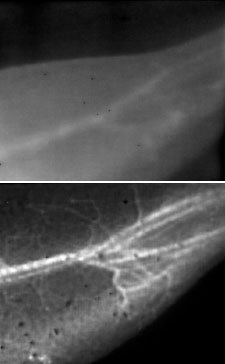

این محققان با استفاده از یک تکنیک ابداعی تصویربرداری فلورسنت این امکان را فراهم کردند که ضربان امواج رگهای خونی حیوانات زنده را با وضوح بی سابقه مشاهده کنند.

در مقایسه با تکنیکهای تصویربرداری عادی، این تکنیک میزان تصویری بسیار شفاف از جریان خون ارائه میکند.

این تکنیک که از آن با عنوان تصویربرداری نزدیک مادون قرمزII یا NIR-II یاد میشود نیازمند تزریق محلول آبی با استفاده از نانولولههای کربن به جریان خون است.

پس از آن محققان یک لیزر را که نور آن در برد نزدیک مادون قرمز ( طول موج حدود 0.8 میکرون) روی حیوان، که در این مورد یک موش بود، قرار دادند.

این نور موجب میشود که نانولولههایی که به طور خاص برای طول موجهای بلندتر از 1 تا 1.4 میکرون طراحی شده نور را منعکس کنند که در نتیجه آن ساختار رگهای خونی مشخص میشود.

نور نانولولهها در طول موجهای بسیار بلندتر از تکنیکهای تصویربرداری عادی برای به دست آوردن تصاویر واضح از رگهای کوچک خونی مهم است. طول موجهای بلندتر نور پراکندگی کمتری دارند و تصاویر واضحتری از رگها ارائه میکند.